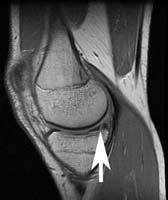

Arthroscopic meniscus repair is an outpatient surgical procedure to repair torn knee cartilage. The torn meniscus is repaired by a variety of minimally invasive techniques and requires postoperative protection to allow healing. Physical therapy is useful to regain full function of the knee, which occurs on average 4-5 months after surgery.

Torn knee cartilage generally produces pain in the region of the tear and swelling in the knee joint. These symptoms are made worse with pivoting motions, squatting, and vigorous activities. Torn meniscus fragments can get caught in the knee joint and cause catching sensations. If a large enough fragment becomes lodged between the bearing surfaces, the knee may ‘lock’ and become unable to be fully bent or extended.

The goal of meniscus surgery is to preserve healthy meniscus tissue. A meniscus tear requires a blood supply to heal. Only the outer third portion of the meniscus has blood supply to enable healing of a tear. Repairs are generally limited to this peripheral region of the meniscus.